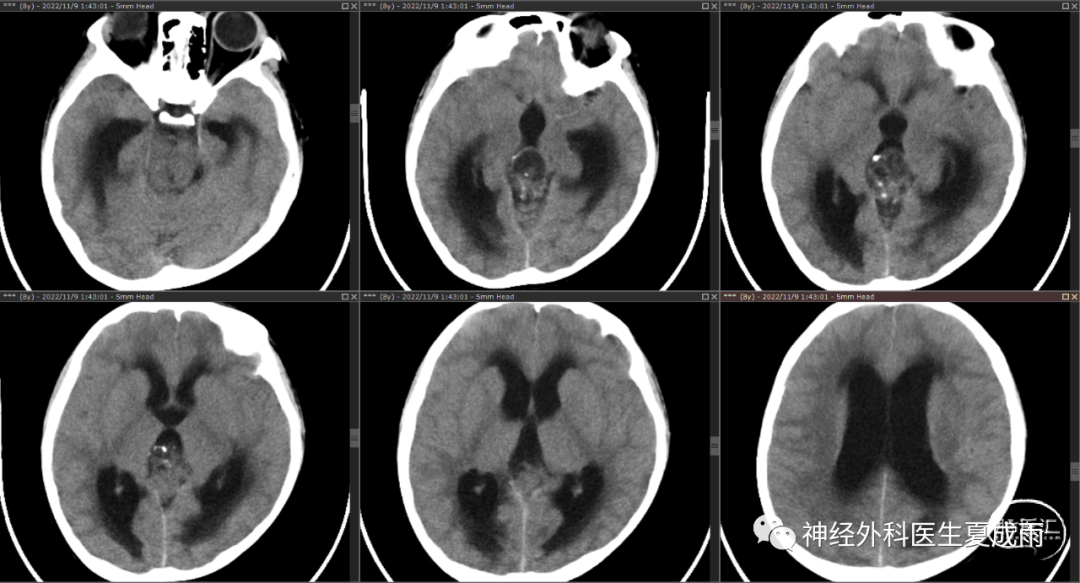

头颅CT⏬

8岁男童,河南息县人,头痛头晕伴恶心呕吐10天,当地医院开始按“胃肠炎”,对症处理未见明显缓解,头晕加重,查头颅CT发现颅内肿瘤伴梗阻性脑积水,经亲友通过医生朋友联系笔者,于2022年11月8日连夜急诊来我院。入院查体精神萎靡,头晕明显,呕吐,视力下降,随时脑疝死亡!